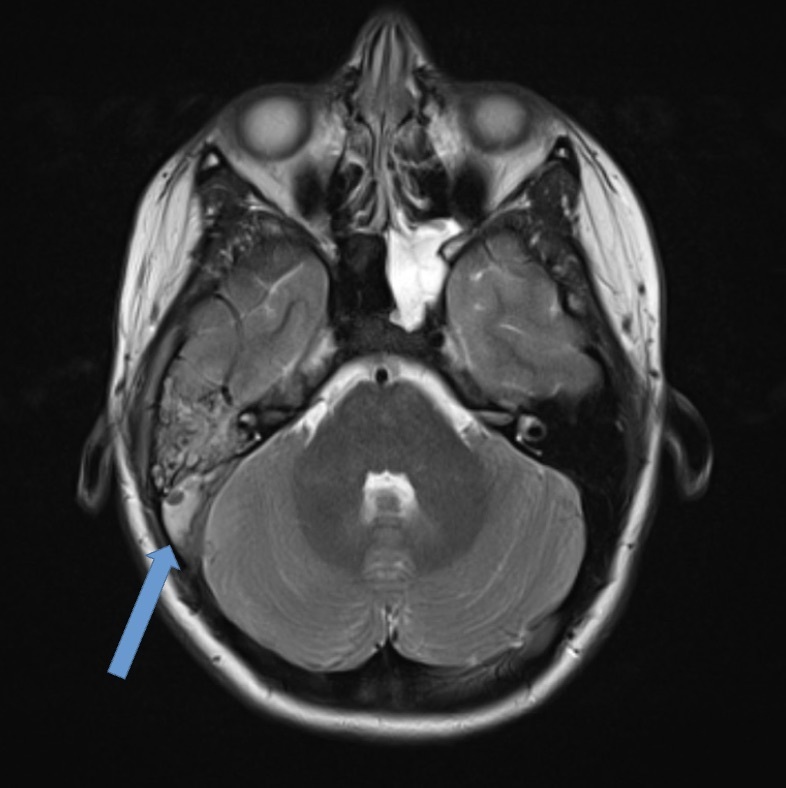

On presentation, she was afebrile and mildly tachycardic. Physical exam revealed a bulging right tympanic membrane with a purulent effusion, tenderness anterior to the sternocleidomastoid, and cheek swelling. There was no notable mastoid tenderness or neurologic deficits. Complete blood count (CBC), complete metabolic panel (CMP), C-Reactive protein (CRP), and procalcitonin were within normal limits. Blood cultures were negative. Computed tomography (CT) neck revealed right mastoiditis with dehiscence along the posterior wall of the right mastoid air cells (Figure 1) and concern for IJV thrombus. Hematology and otolaryngology were subsequently consulted. The patient was started on enoxaparin, along with meningitic-dosed vancomycin, metronidazole, and cefepime. Magnetic Resonance Imaging (MRI) and magnetic resonance venogram (MRV) of the internal auditory canals were obtained which demonstrated ipsilateral otomastoiditis with thrombosis of the right distal transverse and sigmoid sinuses (Figure 2) and proximal right IJV (Figure 3) as well as concern for cerebellar cerebritis with presence of an epidural abscess (Figure 4). The patient underwent a myringotomy with tube placement and mastoidectomy with drainage. Intraoperative findings were significant for middle ear purulence, granulation tissue in the mastoid cavity and a small sigmoid sinus defect where purulent drainage was identified. Intraoperative cultures were positive for Streptococcus pneumoniae resistant to clindamycin, erythromycin, penicillin, tetracycline, and trimethoprim-sulfamethoxazole. Ophthalmology was consulted to evaluate for papilledema, where grade one optic disc edema was noted. After post-operative recovery, she was discharged with a PICC line for 42 days of intravenous vancomycin and ceftriaxone, oral metronidazole, along with 6 months of enoxaparin for anticoagulation.